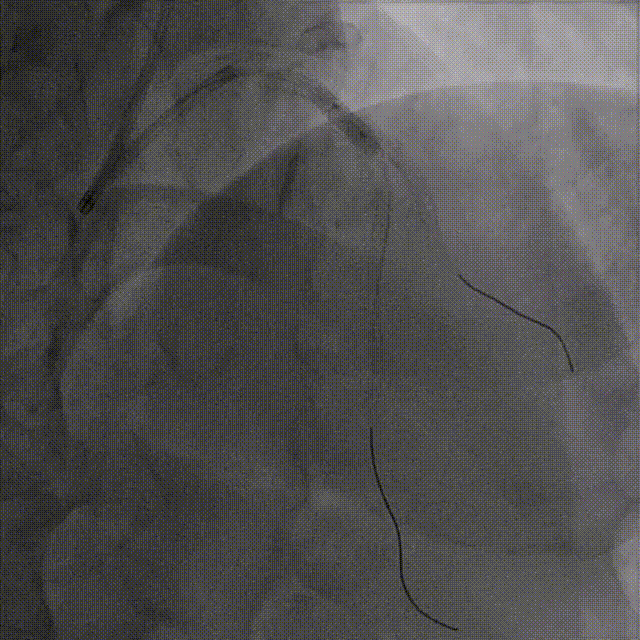

处理D1-LAD支架

LAD导丝交换为工作导丝,D1送入2.75*12mm、2.75*15mmNC球囊依次扩张病变处

LAD送入2.0*15mm、2.5*12mmNC球囊扩张病变处

复查IVUS可见:LAD多处环形钙化,原支架贴壁不良,支架远端导丝走形在支架外,IVUS指导下重新调整导丝进入支架